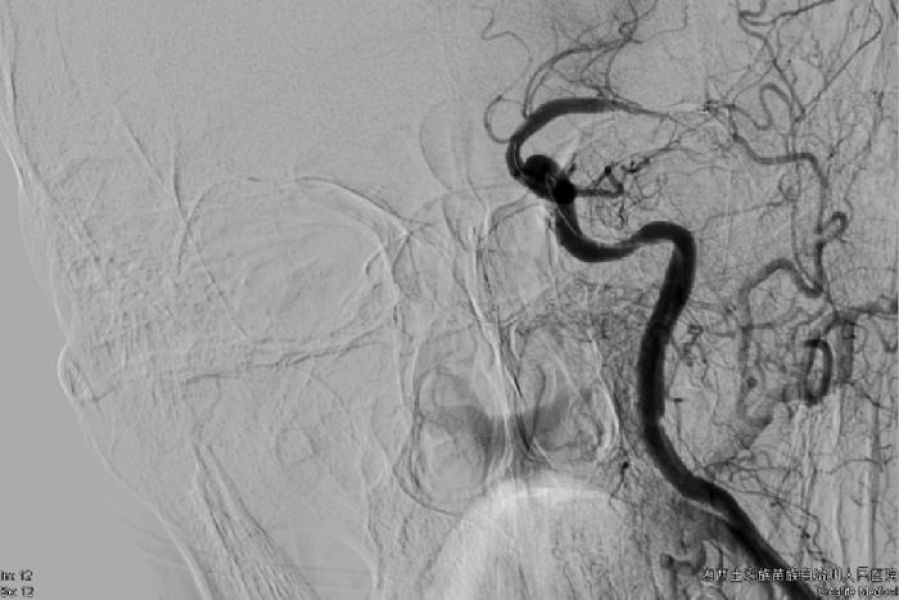

由于当时医院两台DSA都有手术,时间就是大脑,每延迟一分钟开通血管,大脑细胞就有近200万个细胞死亡。经过积极协商,其他科室也很理解的将常规介入手术后延,迅速空出一台DSA机,在16:35 将患者安全送入DSA室进行急诊介入治疗。田勇副主任医师、梁承财主治医师和介入科护士及技师熟练的配合,有条不紊而又迅速完成消毒,铺单,股动脉穿刺,脑血管造影,明确血栓堵塞左侧大脑中动脉主干,患者左侧大脑前动脉A1段先天性缺如,右侧大脑前动脉A1供应双侧大脑前A2及以远血供,造影结果再次确认患者非常适合支架动脉内取栓。经过两次动脉支架植入血栓-静置-回抽拉栓,取出一块红色混合血栓,有部分血栓残留在大脑中动脉分支起始部,患者闭塞血管前向血流完全恢复正常,成功将患者从死神手中挽救出来。术后第二天,患者清醒,手脚可勉强抬起,肌力恢复到3级,术后第三天,患者可自行行走,右侧肢体肌力恢复到4级。目前患者已经康复无残疾出院。

术前